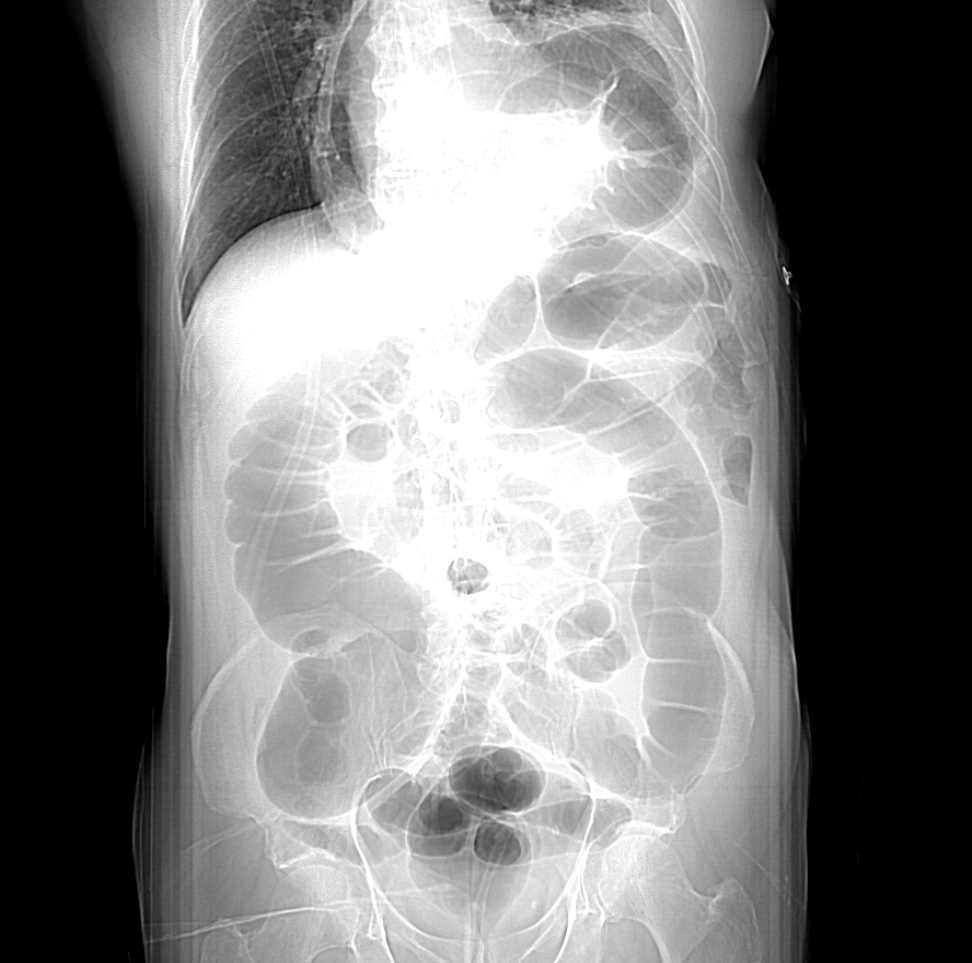

Given the finding of nodular lung opacities, a contrast-enhanced chest CT scan was ordered. A pre-CT scout radiograph (Figure 3) showed a hernia containing stomach, colon, and the tail of the pancreas. There was no axillary, mediastinal, or hilar lymphadenopathy. There was no pleural or pericardial effusion. The central airways were patent. There was left upper lobe, left lower lobe, and right lower lobe compressive atelectasis.

Figure 3. A pre-CT scout radiograph showed hernia containing stomach, colon and tail of pancreas with left upper lobe, left lower lobe, and right lower lobe compressive atelectasis.